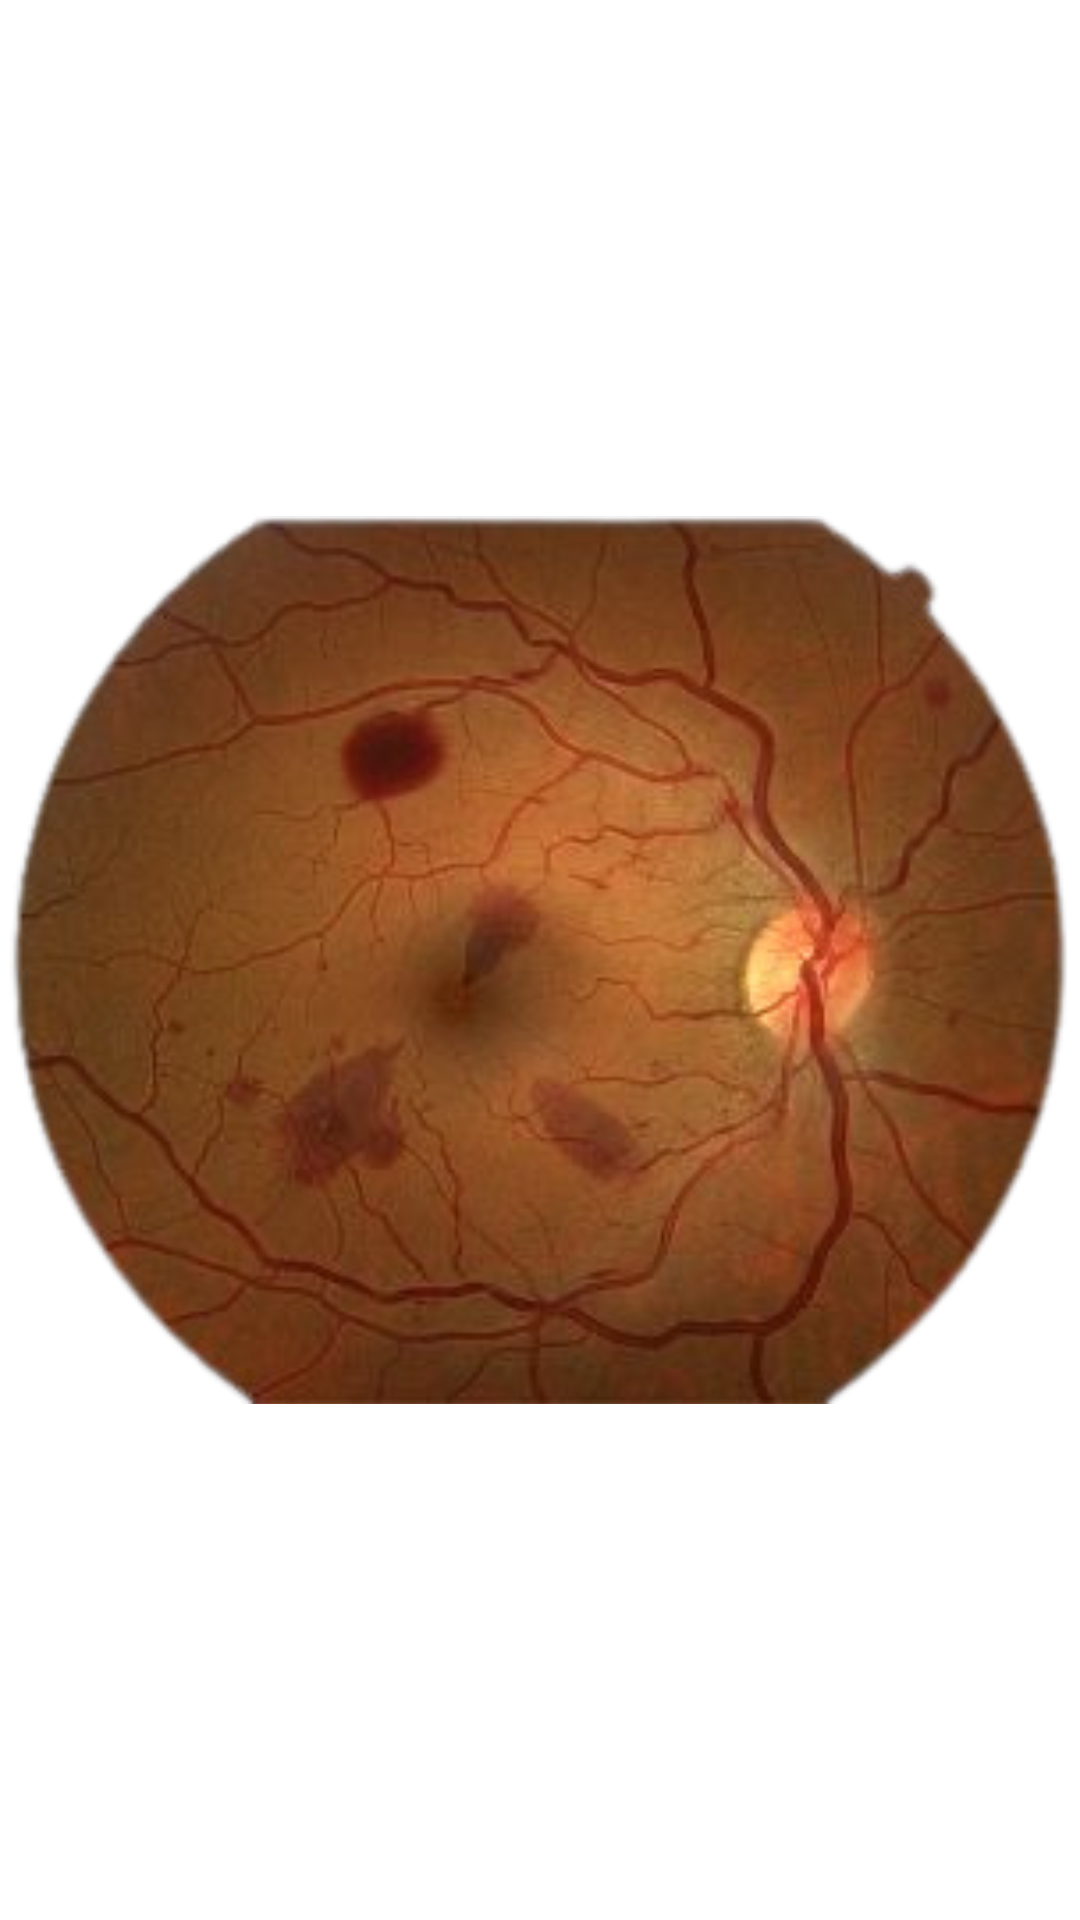

Our Optometrists uses advanced imaging technology such as a retina camera to examine the back of your eye, including the retina, optic nerve and blood vessels.

This helps detect early signs of conditions like glaucoma, macular degeneration, diabetic retinopathy, and other eye diseases that may not show noticeable symptoms until they progress.